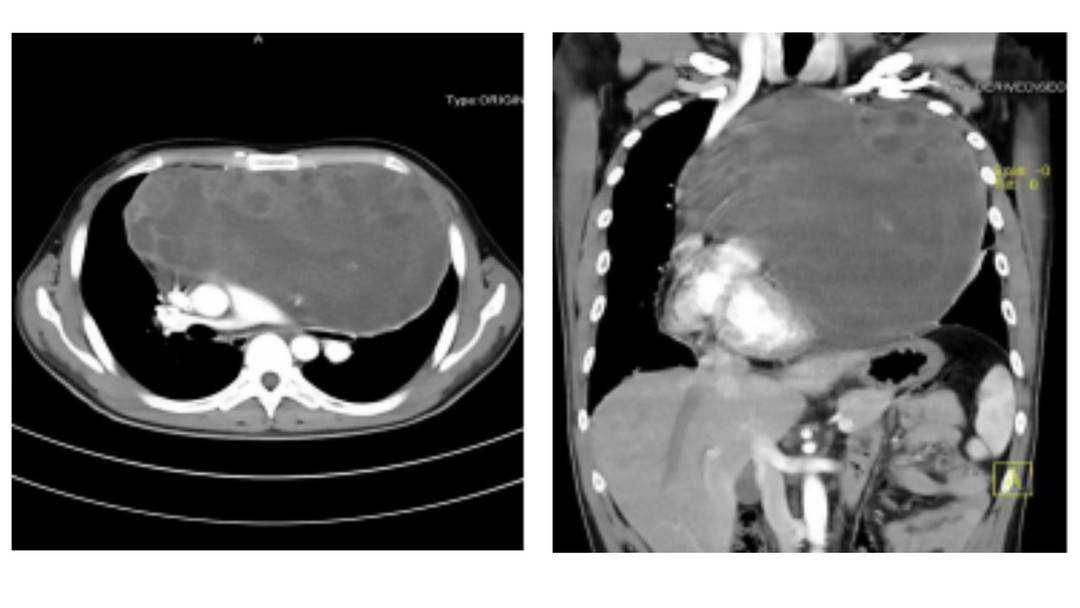

近日,四川大学华西医院肺癌中心周清华教授团队克服重重挑战,通过5个小时手术,为一例纵隔肿瘤压迫心脏、侵犯心包,伴肺功能极重度受损的29岁男性患者,成功摘除重达8.7kg、接近足球直径大小的罕见巨大恶性肿瘤。

因为想取出一颗大个头的纵隔生殖细胞瘤,术中保证患者生命体征稳定、完整切除肿瘤和受侵的组织器官,同时保证肿瘤不复发、患者术后器官各项功能可正常恢复,单是手术过程就十分复杂了,需要主刀医生具有非常强的传统外科手术技术。本次周清华教授救治这位病人时就在短短5小时内实施了纵隔肿瘤切除、部分心包切除术、心包补片修补重建、左肺上叶前段切除术、左肺上叶下舌段切除术五项操作。

针对纵隔生殖细胞瘤这类疾病,目前主要措施就是利用胸部增强CT早期诊断,一旦确诊就立即进行治疗,包括根据肿瘤大小、部位,对邻近组织器官侵犯、推移压迫情况不同,采取直接手术或先辅助化疗、放疗等措施后再手术,并没有有效的预防方法。